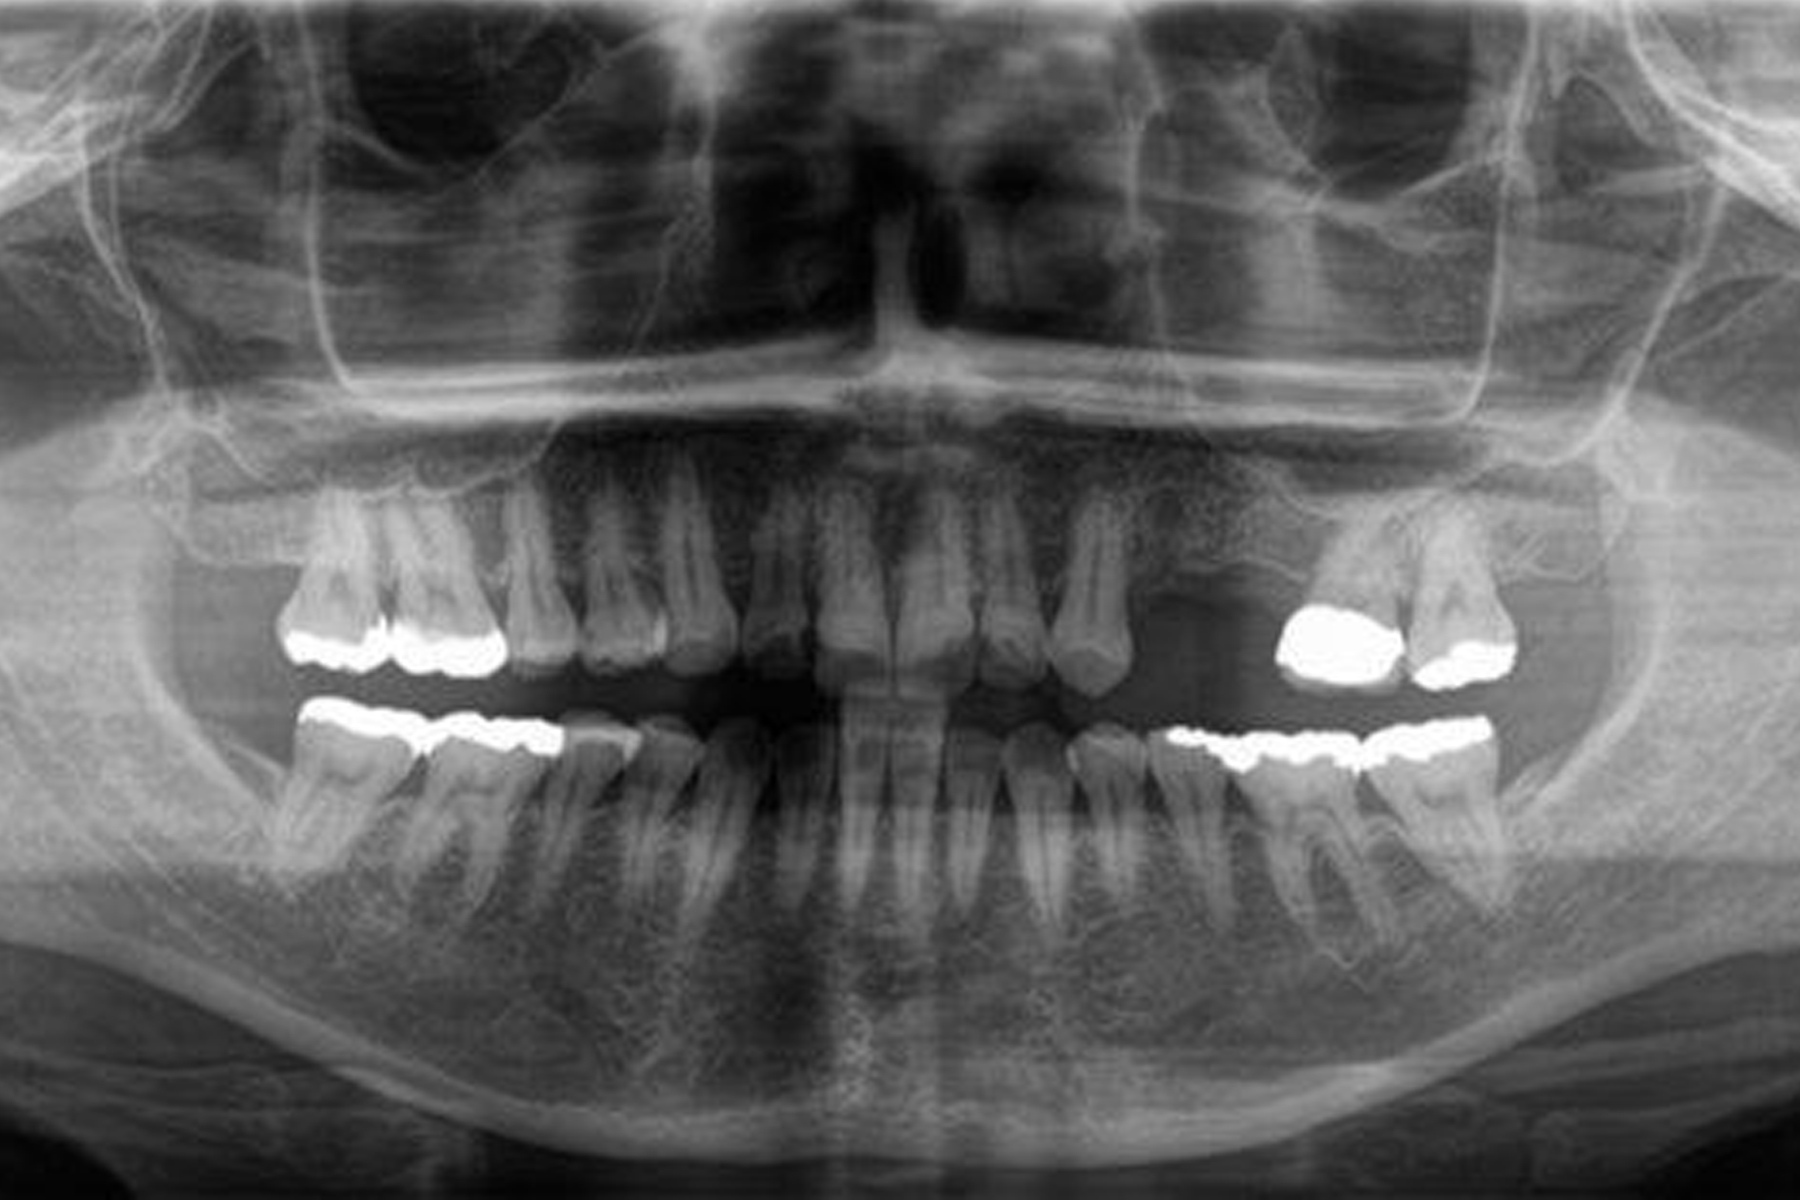

1事前検査

インプラント治療を始める前には、慎重な事前検査が必要になります。レントゲン撮影・CTスキャン・口腔内模型検査などによる充分な検査を行い、綿密な治療計画を立てます。患者さまの同意を得てから手術の日程を決めます。

| 担当医 | 林 大貴 |

|---|---|

| 主訴 | 左上の歯が噛むと痛い |

| 期間 | 約9ヶ月 |

| 治療内容 | 左上4、5番の欠損部位に対して、人工歯根を埋入し上部構造として補綴物をかぶせた。左上4番についてはインプラント埋入の際にソケットリフトを行った。 |

| 治療に伴うリスク | インプラントは、過剰な咬合力がかかった場合、インプラント周囲炎により骨の吸収を認めることがある。 インプラント周囲炎の可能性があるためメンテナンスが必要。 |